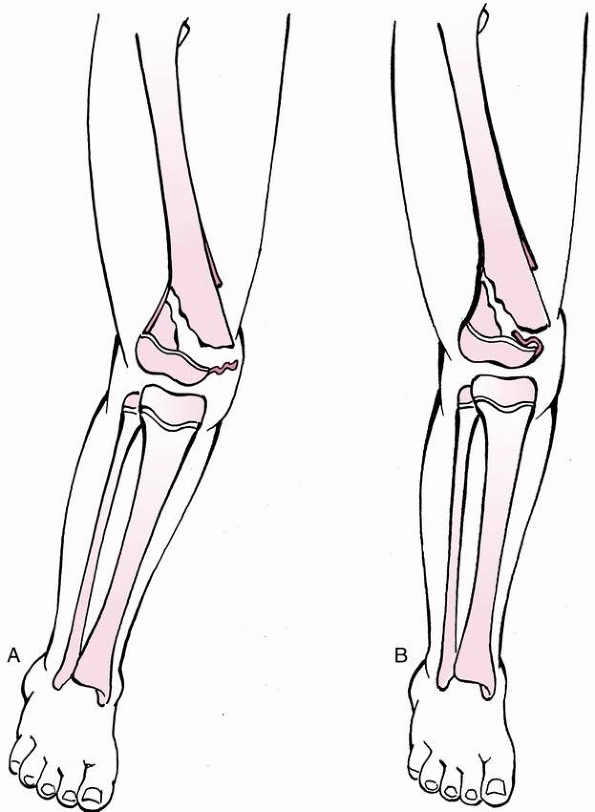

In the adolescent age group, valgus and torsional injury during sports

are a common cause of distal femoral epiphyseal separation (Fig 23-2).

stress across the knee joint. In skeletally mature individuals, this

mechanism of injury can cause ligamentous disruption because ligaments

commonly fail before bone fails when a bending stress is applied across

the knee joint (Fig. 23-3A). However, loading

to failure across the immature knee is more likely to lead to physeal

failure due to tensile stresses that are transmitted through the

ligaments to the adjacent physis (Fig. 23-3B).45

FIGURE 23-2 Valgus and torsional stress across the knee may cause a ligament injury or physeal separation.

FIGURE 23-3 A. In a skeletally mature patient with closed physis, tensile failure usually occurs across the ligament. B.

In a skeletally immature patient with open physis, failure usually occurs across the physis. (Reprinted with permission from Skaggs DL, Flynn JF. Trauma about the knee, tibia, and foot. In Skaggs DL, Flynn JF, eds. Staying out of Trouble in Pediatric Orthopaedics. Philadelphia: Lippincott Williams & Wilkins; 2006.) |